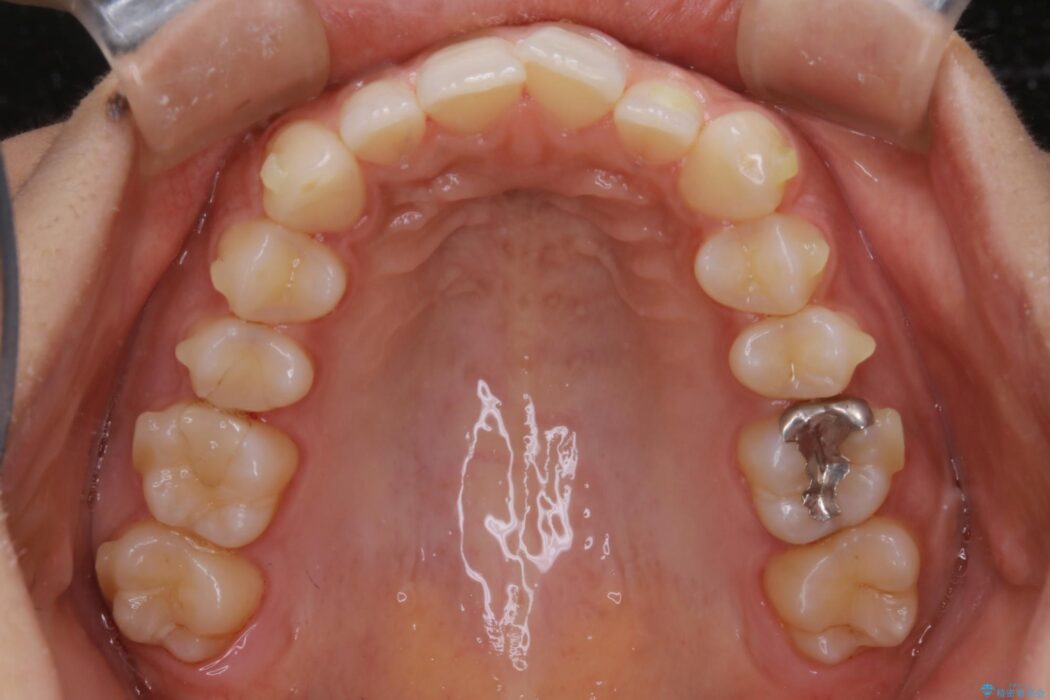

気になるガタツキと噛み合わせを改善したいとご来院されました。

下の歯列よりも上の歯列が前に出ている状態を治すため、マウスピース矯正に加え、患者様にゴムかけのご協力をいただきました。その結果、ガタつきが改善し、上下の噛み合わせが適切な位置で合うようになりました。